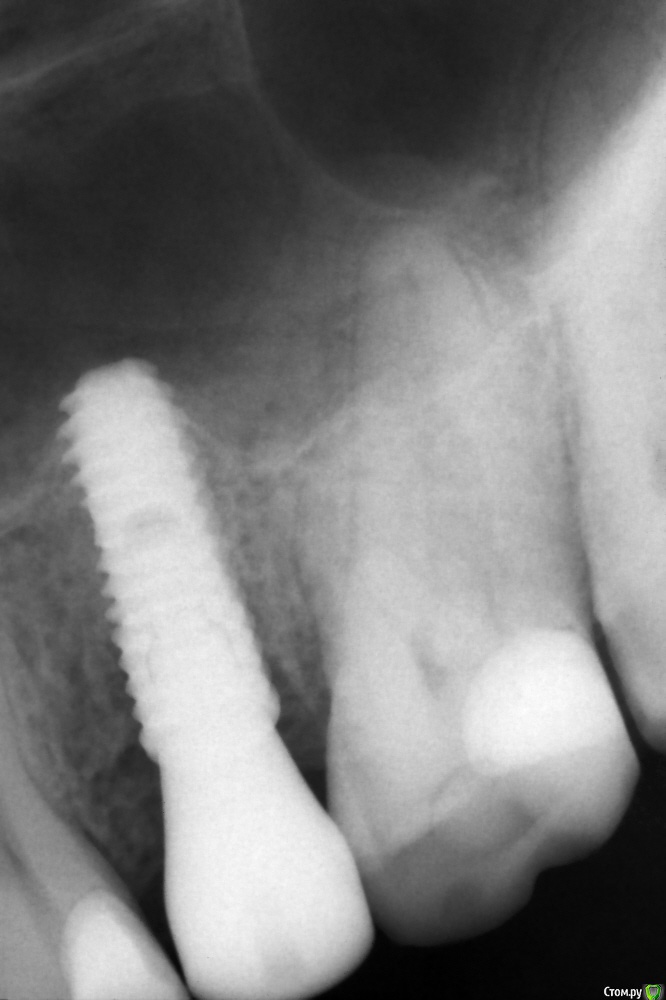

колесников Опубликовано 10 апреля, 2016 Поделиться Опубликовано 10 апреля, 2016 Бюджетная была работа. Без графта,без прф,без сст. Удаление 25 с дефектом кости и в период обострения. Через 3 мес имплантация (осстем 4.0х11.5) и закрытый синус без графта (пациент не потянул). Решил проверить на сколько нарастёт кости чисто на сгустке, при поднятии мембраны на 3-5 мм (не ровное дно). Торк был 35-40 -фдм сразу. Гребень остался широким,сст не стал подшивать,перекинул лоскут с гребня. Через 5 мес наросло 2-4 мм. 5 Ссылка на комментарий

колесников Опубликовано 14 апреля, 2016 Автор Поделиться Опубликовано 14 апреля, 2016 Прям уж закрытый синус? По фото - элементарная бикортикальная фиксация имплантата. Главное - не хамить с пазухой, ибо , торчащий сквозь слизистую винт - прекрасная база для колонизации грибов.Закрытый-это когда закрытый. Отодвинул мембрану через лунку . На снимке видно что имплант не зияет в пустоте и притоплен субкрестально. Ни с какой стороны на бикортикальную не тянет. И кстати про хамить и колонизацию(фамилии не вспомню,может кто поможет),на конференциях часто встречал снимки итальянского спеца -любителя поставить имплант в пазуху на 10 и более мм без прикрытия. 1 Ссылка на комментарий

колесников Опубликовано 14 апреля, 2016 Автор Поделиться Опубликовано 14 апреля, 2016 Согласен с предыдущим комментарием...это бикортикальная фиксацияНе соглашусь. Хотя у меня и не кт,крыть нечем,но видно что над имплантом тень,т.е. он не зияет изначально. И без полипов в итоге-значит имплант не находился в утолщённой шнейдеровой. У вас ,кстати, ведь тоже 3-4 мм наросло? Ссылка на комментарий

Чертков Александр Опубликовано 18 апреля, 2016 Поделиться Опубликовано 18 апреля, 2016 Отодвинул мембрану через лунку Тогда конечно закрытый. Я же не знал этой детали, в стартовом Вы этого не указали 3-4 мм наросло 4-7 Ссылка на комментарий

колесников Опубликовано 20 апреля, 2016 Автор Поделиться Опубликовано 20 апреля, 2016 4-7 Можно снимок "до" и на снимке "после"сместить курсор дистальнее на 2 мм. (Я не привязываюсь. Хочу разобраться,чтобы в перспективе планировать. Есть мысль:когда "подбиваешь" дно нарастает сколько необходимо и апекс покрыт кортикалкой,если мягко поднять- мембрана "обвисает" на апексе и нарастает не более 3мм). Ссылка на комментарий

Чертков Александр Опубликовано 21 апреля, 2016 Поделиться Опубликовано 21 апреля, 2016 Можно снимок "до" и на снимке "после"сместить курсор дистальнее на 2 мм. (Я не привязываюсь. Хочу разобраться,чтобы в перспективе планировать. Есть мысль:когда "подбиваешь" дно нарастает сколько необходимо и апекс покрыт кортикалкой,если мягко поднять- мембрана "обвисает" на апексе и нарастает не более 3мм).http://s010.radikal.ru/i312/1604/ec/5c9cacf33ca2.jpghttp://s019.radikal.ru/i624/1604/2d/6b259ffd5f86.jpgТак? 4 Ссылка на комментарий